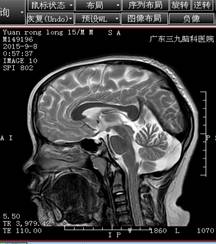

结合小袁的病史,神经内二科的钟水生主任考虑其存在垂体柄阻断综合征的可能(图一),并建议补充垂体薄层平扫+增强扫描(图二)。完善检查后,钟主任给予小袁B族维生素、申捷促进神经修复等对症治疗。

头颅MRIT2+增强(矢状位)+FLAIR(图一)

4、MRI特征性影像表现包括:垂体柄的完全性缺如或明显变细,T1WI垂体窝后部正常或垂体后叶于第三脑室漏斗隐窝或正中隆起处可见到异常垂体后叶的小斑片状、小结节状高信号,这是PSIS的特异性征象,也是诊断要点;垂体前叶不同程度萎缩变薄,结构显示不清,甚至消失。